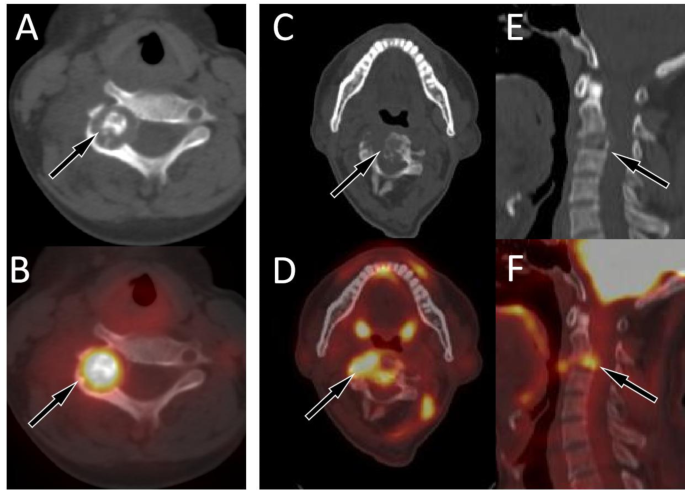

Our study included 11 patients with osteoblastoma originating from the spine, with the median age of onset being 14 years old. The lesions were most commonly distributed in the cervical spine, with the majority of lesions located in the posterior elements. Osteoblastoma had a small volume and can also show expansive bone destruction on CT, but the bone cortex is usually intact and accompanied by sclerotic rims. The center of the lesion usually shows residual bone ridges or characteristic high-density calcifications (Fig. 3A, B). These lesions showed an increased 18F-FDG uptake on PET, with a mean SUVmax of 6.7 ± 2.4, which is slightly lower than the SUVmax reported in the literature13. The epicenter of a few lesions may occur in the vertebral body, and accompanied by pathological compression fractures of the vertebral body (Fig. 3C–F).

(A,B) A 10-year-old girl with typical PET/CT findings of osteoblastoma; (A) Axial CT revealed osteolytic bone destruction in the right vertebral plate of the fifth cervical vertebra, with nodular ossification at the center of the lesion (arrow); (B) The PET/CT fusion image of the corresponding area shows increased 18F-FDG uptake (arrow), with a SUVmax of 8.1. (C–F) A 18-year-old man with atypical PET/CT findings of osteoblastoma; (C) Axial CT revealed osteolytic bone destruction in the fourth cervical vertebra, with the main lesion located in the vertebral body and multiple residual bone ridges visible within the lesion (arrow); (D) The PET/CT fusion image of the corresponding area shows increased 18F-FDG uptake (arrow), with a SUVmax of 6.8; Sagittal (E CT; F PET/CT) reveals compressive changes of the vertebral body (arrows).